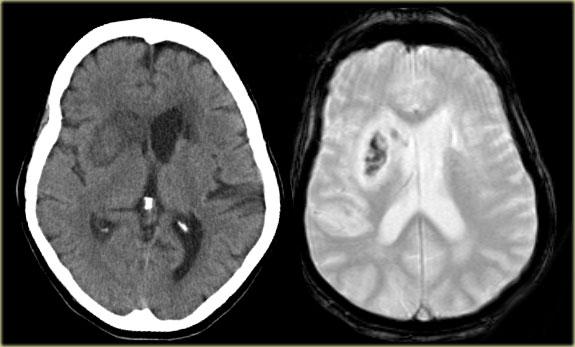

Bên trái là hình ảnh CT của nhồi máu PICA bên trái.

Lưu ý sự lan rộng về phía sau.

Nhồi máu là hậu quả của một trường hợp bóc tách động mạch (mũi tên xanh lam).

Bên trái là hình ảnh MRI của nhồi máu PICA bên trái.

Trong các trường hợp nhồi máu một bên, luôn có sự phân định rõ ràng tại đường giữa do các nhánh nhung mao trên không vượt qua đường giữa mà đi theo hướng dọc (sagittal).

Sự phân định rõ ràng này có thể không biểu hiện cho đến giai đoạn muộn của nhồi máu.

Trong giai đoạn sớm, phù nề có thể vượt qua đường giữa và gây khó khăn cho chẩn đoán.

Nhồi máu ở mức cầu não thường có vị trí cạnh đường giữa và được phân định rõ ràng do các nhánh của động mạch nền đi theo hướng dọc và không vượt qua đường giữa.

Nhồi máu hai bên hiếm khi được ghi nhận do những bệnh nhân này thường không sống đủ lâu để được thăm khám, nhưng đôi khi có thể thấy các ổ nhồi máu nhỏ hai bên.